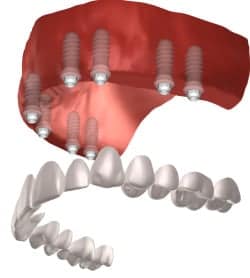

Dr. Rajaski and Dr. Adams are long time friends from the University of Maryland Dental School going all the way back to 1997. Dr. Rajaski has practiced in private practice and at the University of Maryland Dental School as a part time faculty member. Maryland Holistic Dentist is happy Dr. Rajaski as one of our full time providers. Dr. Rajaski is a member of the IAOMT (International Academy of Oral Medicine and Toxicity) and is board certified as a dentist and a dental sedation professional. Dr. Rajaski is a holistic-minded doctor and combines a variety of biological and conventional techniques into his practice. Dr. Raski recognizes that the oral cavity is central to overall health. He implements many holistic techniques to his treatments such as platelet rich fibric (Dental PRF), ozone and non-metal zirconia implants.